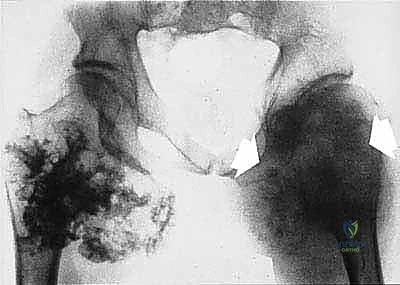

جراحة الحفاظ على الأطراف (Limb-Salvage Surgery): الفن والعلم

تعتبر جراحة الحفاظ على الأطراف معجزة طبية حديثة. بدلاً من بتر الطرف المصاب، يقوم الأستاذ الدكتور محمد هطيف بإزالة الورم بالكامل ثم إعادة بناء العظم والمفصل والأنسجة الرخوة. تتكون هذه العملية المعقدة من ثلاث مراحل أساسية:

المرحلة الأولى: استئصال الورم (Resection)

يتم فتح الجلد والأنسجة بعناية فائقة. التحدي الأكبر هنا هو فصل الورم عن الأوعية الدموية والأعصاب الرئيسية المغذية للطرف. يستخدم الدكتور هطيف تقنيات الجراحة الميكروسكوبية لضمان سلامة هذه الهياكل الحيوية، مما يحافظ على حيوية الطرف وحركته.

المرحلة الثانية: إعادة البناء العظمي (Skeletal Reconstruction)

بعد إزالة جزء من العظم (أو المفصل بأكمله)، يجب سد الفجوة. تتعدد الخيارات التقنية التي يوفرها الدكتور هطيف في صنعاء: